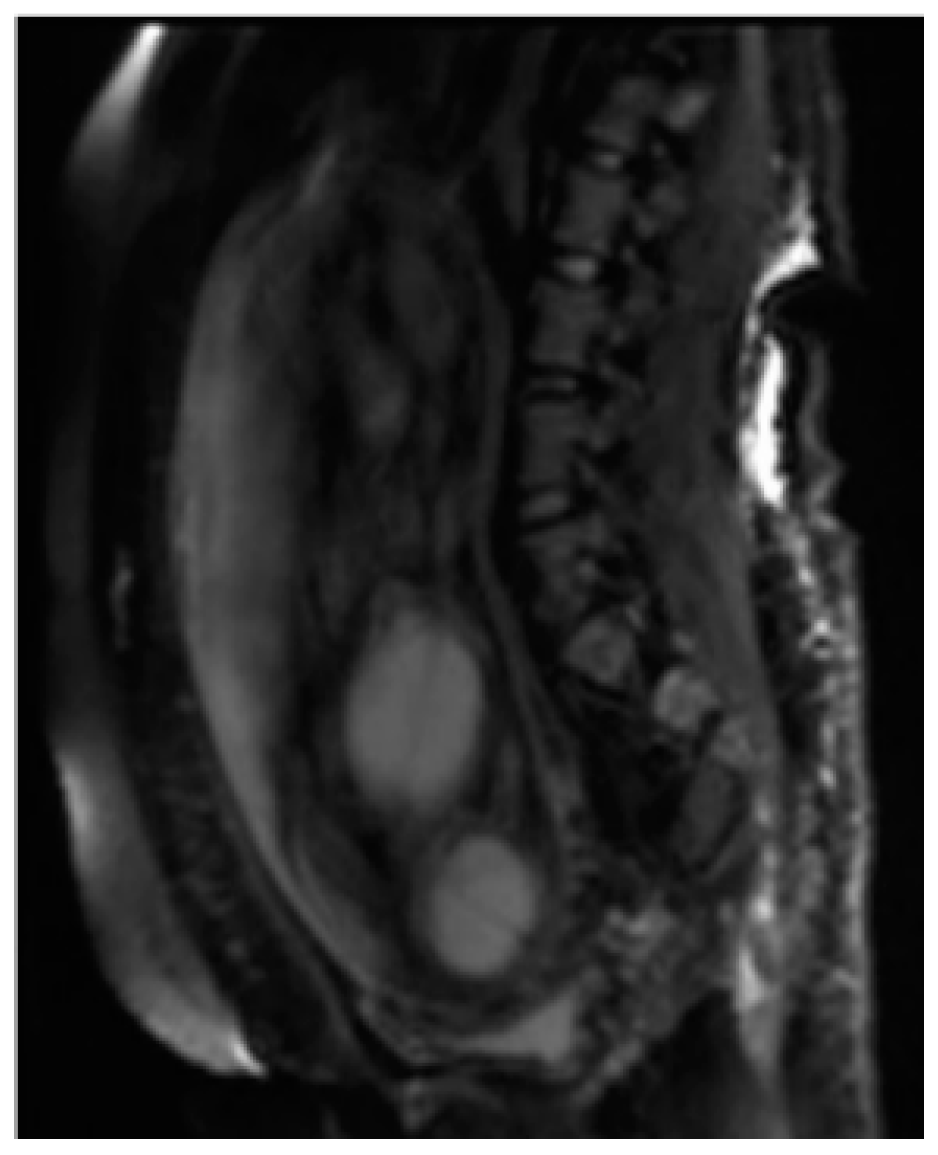

MRI has the greatest advantage in the second and third trimesters of pregnancy to minimize the difficulties due to small dimensions and frequent fetal movements in early management periods, particularly in the third trimester, and it is therefore optimal for the evaluation of anomalies in charge of the cerebral cortex, thanks to a better spatial resolution. Fetal MRI prior to 20 weeks is uncommon. Feto-placental imaging involves the acquisition of different sequences performed on the three planes of space, axial, coronal, and sagittal, some of which are indispensable and others are optionally added depending on the clinical question. The development of fast sequences has allowed for the reduction of motion artifacts, with the possibility of acquiring a series of images in 15/20 s and having a complete acquisition of the exam in around 20–40 min. The MRI examination is preceded by the acquisition of a localizer on the three planes; it is an extremely rapid sequence, of non-diagnostic quality, which allows verification of the position of the placenta in craniocaudal and lateral-lateral and to evaluate the correct coil positioning and identification of landmarks for subsequent acquisitions. Generally, the field of view (FOV) used varies within the 30–40 cm range, and the slice thickness is around 4–6 mm; thin slices of 2–3 mm can be obtained, but the smaller the slice thickness, the lower the signal-to-noise ratio (SNR). Overall, the choice of slice thickness always depends on the management age and therefore on the size of the fetus. The typical matrix is 256 × 256 [12]. The sequences used for feto-placental imaging are the T1 and T2 dependent sequences acquired during respiratory apnea. The T2-weighted sequences provide a greater contrast resolution between the various structures present within the field of view, between the placenta, the amniotic fluid, and the fetuses, which, being structures with different tissue compositions, show a different signal intensity in response to the radio frequency (RF) stimulus (Figure 1).

Figure 1.

Fetal magnetic resonance imaging (MRI) of Twin reversed arterial perfusion (TRAP) sequence. Half-Fourier Acquisition Single-Shot Turbo-Spin-Echo (HASTE) T2 Sag. Both the acardiac (signaled by the arrow) and pump twins are visible.